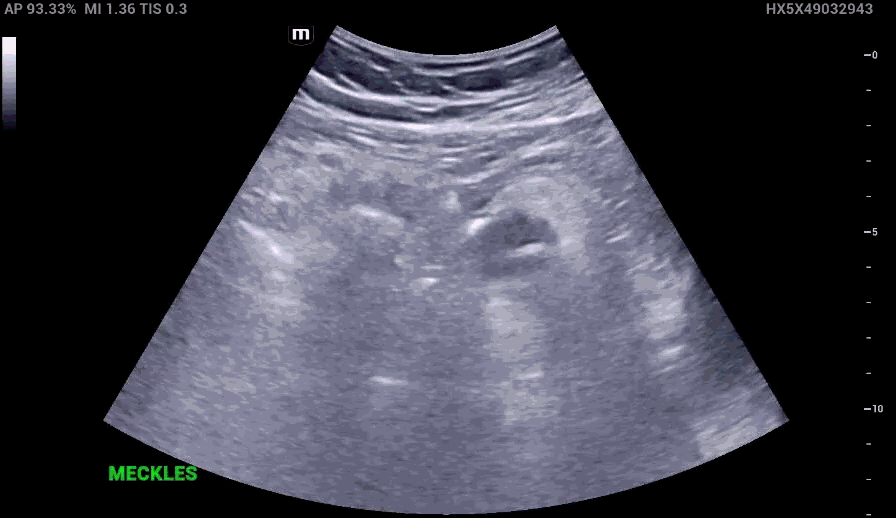

RLQ US:

Remainder of the ED course

Appendcitis was high on the differential with what looked like an appendocolith in the right lower quadrant with posterior acoustic shadowing. CT was ordered which showed the following:

Utilizing Ultrasound in Diagnosing Meckel’s Diverculitis

• Ultrasound has a higher accuracy in pediatric patients than adults in diagnosting Meckel’s diverticuliits, similarly in the setting of appendicitis.

• In a large study involving 784 children, ultrasound demonstrated a sensitivity of 93.6% and a specificity of 98.1%.

The characteristic features of inflamed Meckel’s diverticulum can include the following findings:

• Fixed, blind ending tubular or cystic structure in the bowels.

• Thickened wall

• Irregular mucosal layer

• Tubular hyperechoic structure

• Surrounding hyperechoic fat representing pericolic inflammation

• May contain fluid, air or particulate material

• Hyperemia in the diverticular wall indicating inflammation

• Increased vascularity in the surrounding hyperechoic layer, which suggests perforation

• Small bowel obstruction may be present as a complication

However, many of the above findings in the right lower quadrant can be mistaken for other conditions such as appendicitis and intussusception in the right age group.

There are limitations in ultrasound use in adults as most of the published data involves the pediatric populations.